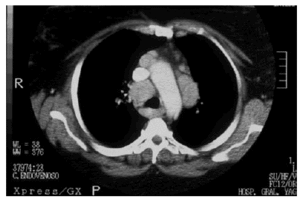

Ante estos hallazgos histológicos se realizó una batería de pruebas complementarias para estudiar la posible afectación sistémica, incluyendo hemograma y bioquímica sanguínea, detectándose los siguientes resultados anómalos: glucosa, 199 g/l; proteína C reactiva, 42; enzima conversora de la angiotensina (ECA), 62. La calcemia y la calciuria fueron normales. Se realizó una prueba de Mantoux, que fue negativa. Las exploraciones de imagen, incluyendo radiografías y TC de tórax, mostraron grandes masas adenopáticas hiliares bilaterales y paratraqueales, que comprimían la tráquea (fig. 4). Las pruebas funcionales respiratorias fueron normales. Tras una valoración oftalmológica, neurológica y cardiaca no se observó afectación de otros órganos.

Fig. 4.--En la TC torácica se observaron adenopatías hiliares y paratraqueales que comprimían la tráquea.